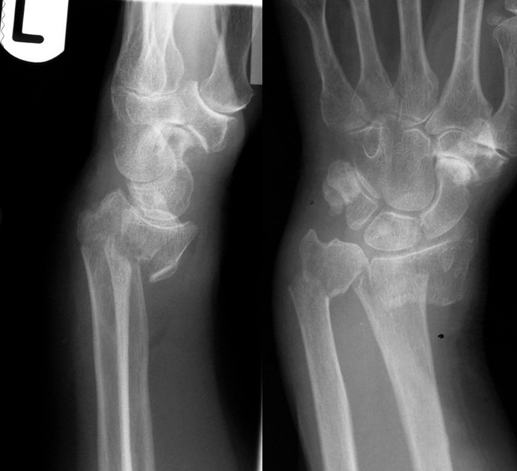

(3)Smith 骨折

桡骨远端屈曲型骨折,骨折远端向掌桡侧移位。